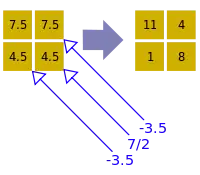

- A basic premise in back-projection is that any attenuation of the X-ray beam has occurred uniformly along the path followed from the source to the detector. Let's consider a simple tomographic slice containing just four voxels to illustrate the computational approach - see Figure 7.11. The first projection, P1 is obtained from a horizontal exposure from left to right in the figure. The back-projection of P1 involves putting the values 7 and 9 in both elements of the first and second rows, respectively. The second projection, P2 adds a 4 to the top right element, 1 to the bottom left element and 11 to the other two elements when it is back-projected. The other projections are treated in a similar fashion. Following regularisation of the data set the final image is obtained at the bottom left of the figure.